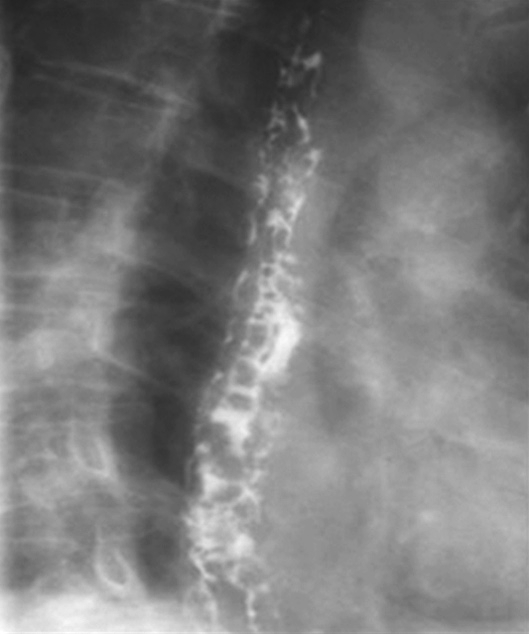

常规腹部平片对肝硬化诊断价值非常有限,但胃肠道钡餐检查可显示中晚期肝硬化患者食管、胃底蚯蚓状扩张的静脉。食管静脉曲张是门静脉高压的重要并发症,最主要见于肝硬化、门脉系统的血栓形成及上腔静脉综合征。

上消化道钡餐检查可见食管及胃底多发串珠状或蚯蚓状充盈缺损,食管腔轻度扩张,管壁蠕动减弱,病变常始于食管下段,后延及食管中段及胃底,极少数可波及食管上段。按静脉曲张的范围、程度及食管蠕动功能分为轻度、中度、重度。①轻度:静脉曲张最初局限性于食管下段,表现为黏膜皱襞稍增宽,可呈浅锯齿样表现。管腔可收缩排空。②中度:随着静脉曲张的发展,曲张范围超过下段累及中段。静脉增粗迂曲突向管腔,正常平行的黏膜皱襞消失,代之以纵行粗大结节样条状影,进一步表现为串珠状或蚯蚓状充盈缺损,食管边缘凹凸不平,由于黏膜下明显静脉曲张,食管腔被撑开而略显增宽,食管收缩欠佳,排空稍延迟。③重度(图5-21-34):后期静脉曲张扩展到中上段,甚至食管全长。严重的曲张静脉占据食管壁,并使肌层受压迫而退变,食管明显扩展,不易收缩,腔内见形态不一的圆形、环状或囊状充盈缺损,管壁蠕动明显减弱,排空延迟,但管壁仍柔软可扩张。

图5-21-34 重度食管静脉曲张钡剂检查结果

食管全长可见不规则蚯蚓状和结节状充盈缺损,食管明显扩展,蠕动明显减弱,排空延迟,管壁尚柔软